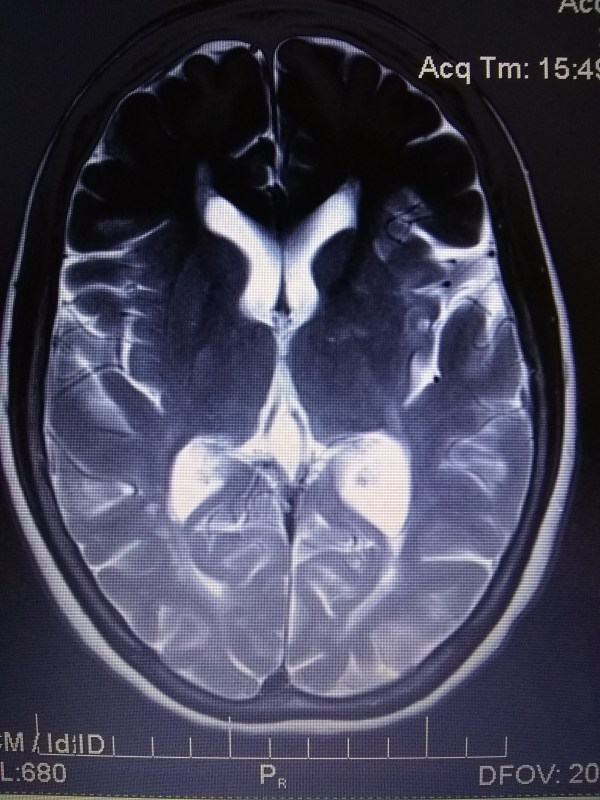

Nuclear Magnetic Resonance Imaging

NMRI 2018 June 18

AXIAL T2

SECTION 2/2

IMAGE 12/24

REPORT 2018 June 25: Sub-acute T2 hypersensitivity, left frontal lobe

TREATMENT 2018 June 25: 60mg oral steroids x 16 days. ACTIVITY 2018 June 25: bedrest x 16 days

and the texture of my brain

whose rippling white matter winds through the warp and grain

and thank you, God, there are no black holes!